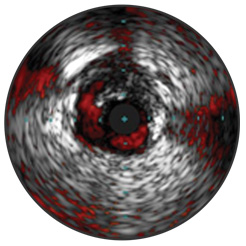

ChromaFlo est disponible sur le système intégré Philips Volcano Core et sur les systèmes Core Mobile, s5 et s5i. Elle permet d’évaluer facilement l’apposition du stent, la dimension de la lumière et autres. L’imagerie échographique ChromaFlo visualise le débit sanguin en rouge par simple pression d’une touche.

ChromaFlo est adaptée aux vaisseaux périphériques et coronaires, y compris l’artère coronaire gauche principale, les bifurcations, l’artère fémorale superficielle et l’artère iliaque. Conçue pour visualiser instantanément la dimension de la lumière et l’apposition du stent, elle aide à identifier les branches, dissections de paroi et thrombus ainsi que la distribution de la plaque au niveau des bifurcations. ChromaFlo est compatible avec les cathéters numériques pour échographie intravasculaire plug-and-play Philips Volcano Eagle Eye Platinum et les cathéters Visions PV 018 et 014.

ChromaFlo visualise le débit sanguin en rouge afin d’identifier :

L’imagerie échographique ChromaFlo est automatiquement enregistrée comme échographie intravasculaire en nuances de gris, permettant l’observation complète du volume de la plaque, du calcium et de la paroi vasculaire.